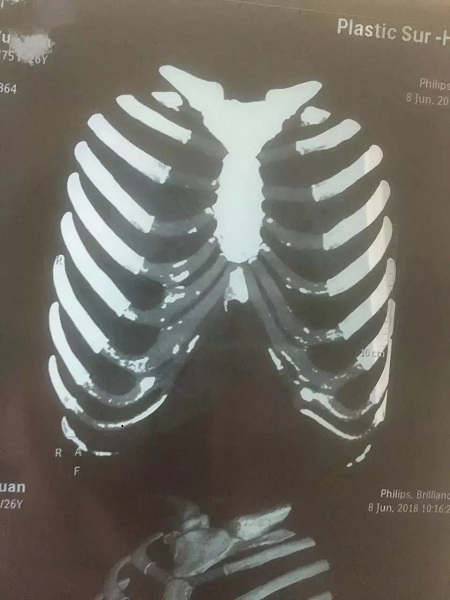

▼鈣化肋軟骨和未鈣化肋軟骨的影像區(qū)別

如上圖所示,鈣化了的肋軟骨和硬骨一樣,都是呈同樣密度的白色顯示,而正常的肋軟骨密度顯示是透明狀。

▼輕微鈣化的肋軟骨

如果肋軟骨鈣化程度比較嚴(yán)重,軟骨已經(jīng)堅(jiān)硬如石,沒(méi)辦法雕刻,那就不建議再做肋軟骨隆鼻了,可以考慮鼻中隔軟骨搭配耳軟骨進(jìn)行鼻綜合整形。